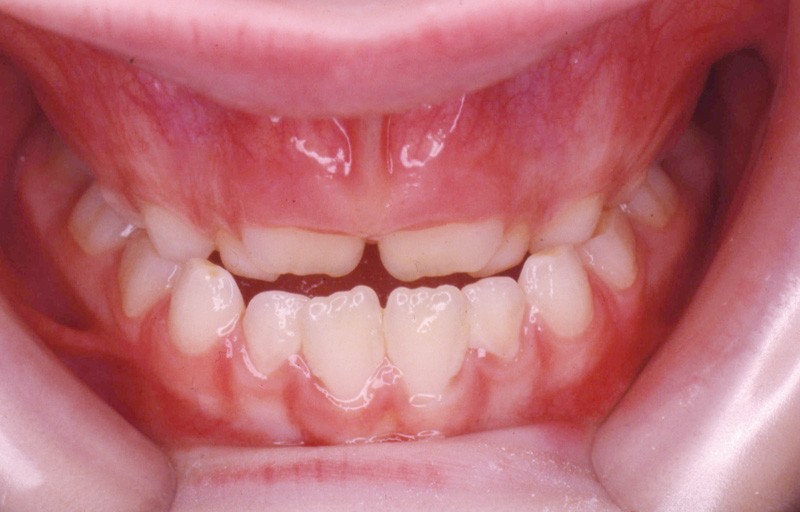

L’examen de la denture (fig. 3 à 5) montre :

• dans le sens antéro-postérieur, des relations molaires et canines de type classe III d’Angle et une inversion des rapports incisifs,

• dans le sens transversal, une endomaxillie bilatérale prédominante dans la région canine.